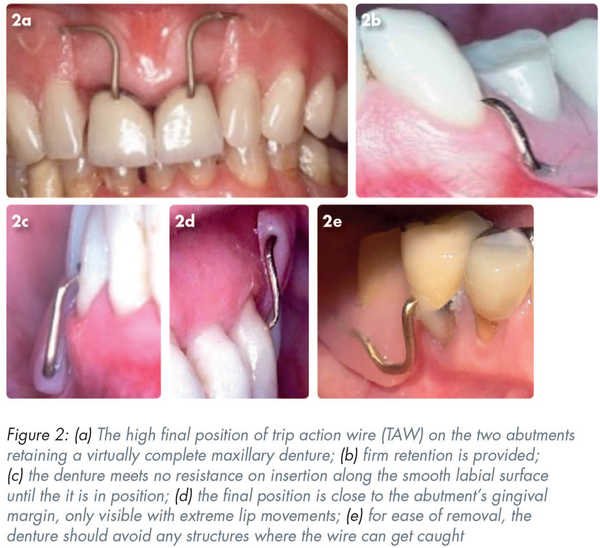

Introduced by Stone the theory was applied by Kabcenell. The reader can demonstrate the phenomenon by moistening the tip of the index finger and sliding it “downwards” along a smooth surface (e.g. a phone or table) and then pushing the finger “upwards”. As the angle of incidence increases, one should be aware of resistance, which increase to a maximum when the finger is at a right angle to the surface. This is the so-called “trip action”. Clinically, it results in the “clasp” on insertion sliding over the buccal/labial surface of the abutment. Removal of the denture is resisted by the “trip action effect”. Although it is inherent in all clasp actions, it is most usefully demonstrated with a 0.9mm round gold wire (trip action wire [TAW]). Figure 2a demonstrates the high final position of TAWs on the two abutments retaining a virtually complete maxillary denture.

it provides firm retention particularly in the absence of undercuts (Figure 2a-b)

as the denture is inserted it offers no resistance along the smooth labial surface until the denture is in position (Figure 2c)

its final position is close to the abutment’s gingival margin, only becoming visible with extreme movements of the lips and thus can be very effective on the labial surface of a canine abutment (Figure 2d)

there is a need to avoid any structures in which wire can get caught as this will obstruct the removal of the denture (Figure 2e). Any irregularities on the facial surface should be polished or covered with a smoothed composite resin addition